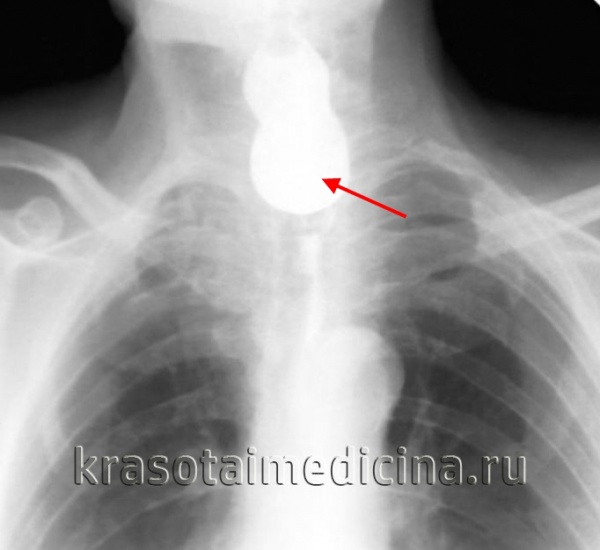

Дивертикул Ценкера на рентгенограмме с барием:

(а) Прямая проекция, слева от средней линии определяется большой круглый мешок, максимальный диаметр около 3 см.

(б) Латеральная проекция. Можно оценить заднюю стенку мешка, наполненного барием.

Определяется стенка между дивертикулом и пищеводом, в которой расположена перстнеглоточная мышца.